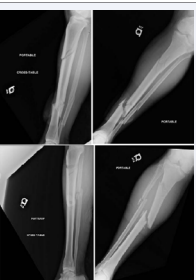

Figure 1: Anterior-Posterior and Lateral initial radiographs of a 49 year-old male who sustained bilateral segmental tibia fractures as a pedestrian stuck by a motor vehicle. The left tibia fracture was classified as a Grade I openfracture.